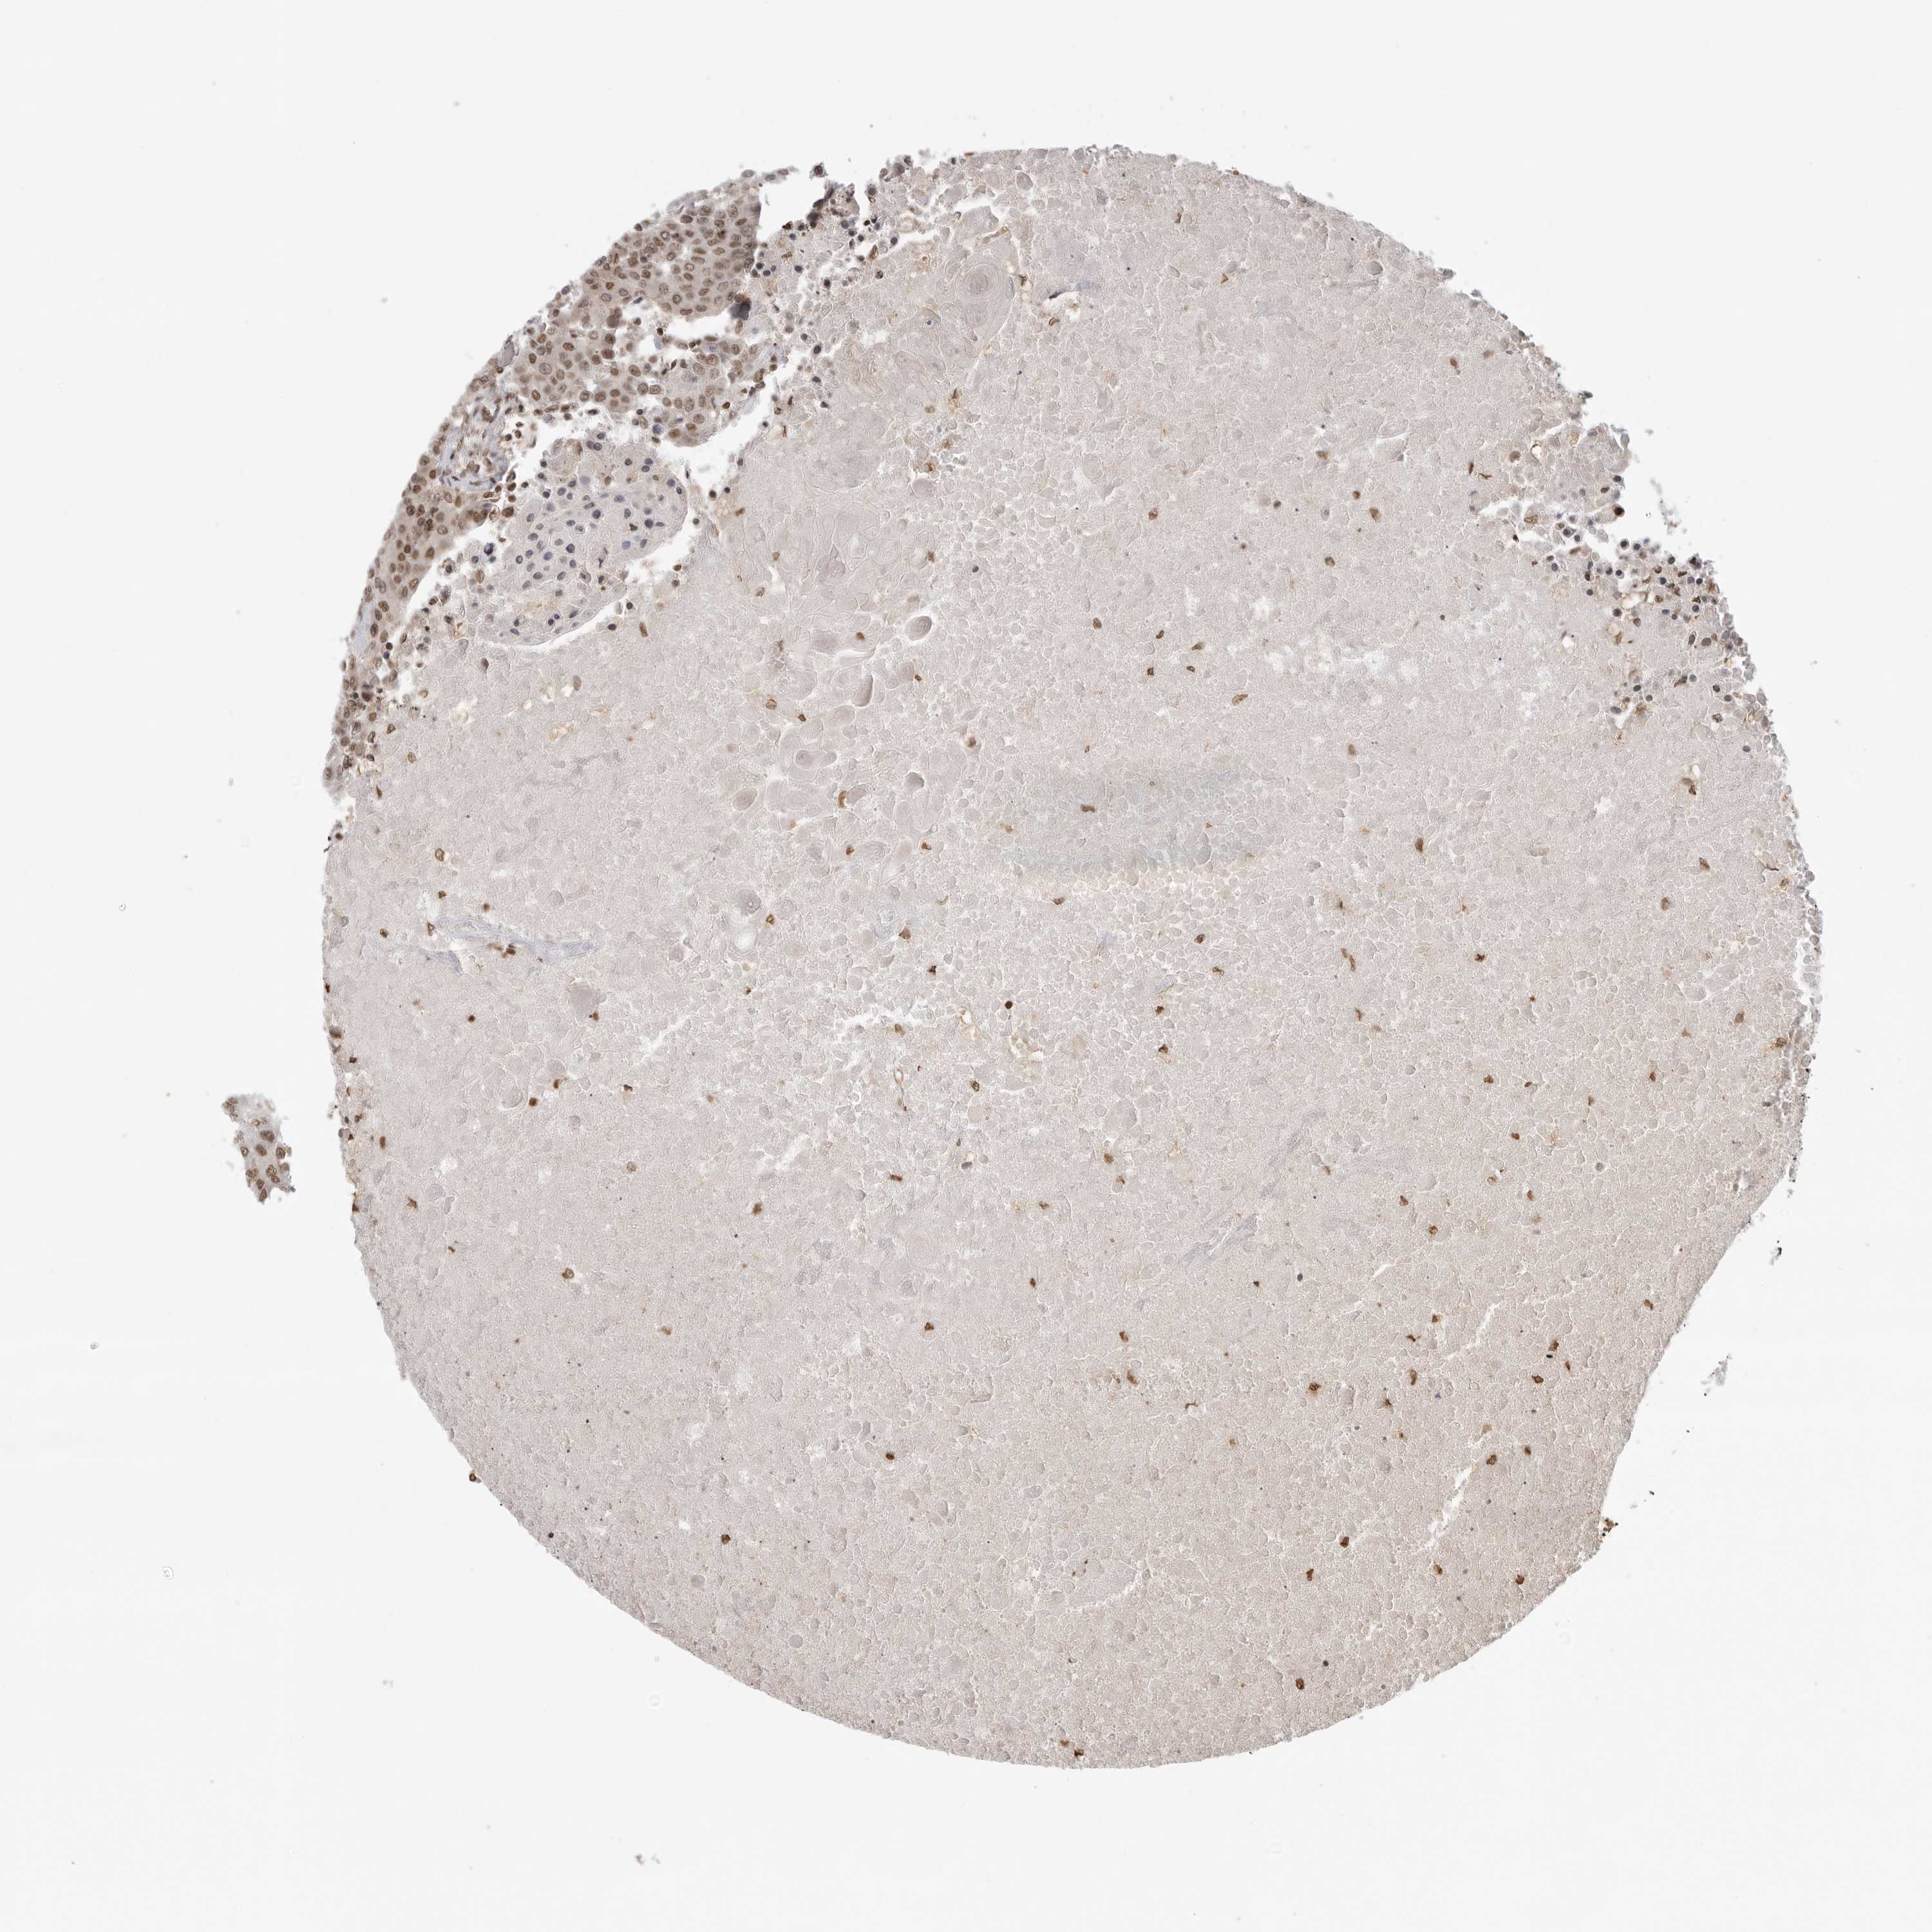

UROTHELIAL CANCER - Protein expressioni

A mouse-over function shows sample information and annotation data. Click on an image to view it in a full screen mode. Samples can be filtered based on level of antibody staining by selecting one or several of the following categories: high, medium, low and not detected. The assay and annotation is described here.

Note that samples used for immunohistochemistry by the Human Protein Atlas do not correspond to samples in the TCGA dataset.

Antibody stainingi

Antibody staining in the annotated cell types in the current human tissue is reported as not detected, low, medium, or high, based on conventional immunohistochemistry profiling in selected tissues. This score is based on the combination of the staining intensity and fraction of stained cells.

Each image is clickable and will lead to virtual microscopy that enables deeper exploration of all samples and also displays staining intensity scores, fraction scores and subcellular localization as well as patient and tissue information for each sample.

Antibody HPA026306

Antibody HPA026309

Antibody CAB016538

Staining

High

Medium

Low

Not detected

Intensity

Strong

Moderate

Weak

Negative

Quantity

>75%

75%-25%

<25%

None

Location

Nuclear

Cytoplasmic/membranous

Cytoplasmic/membranous,nuclear

Urothelial carcinoma, Low grade

Urothelial carcinoma, High grade